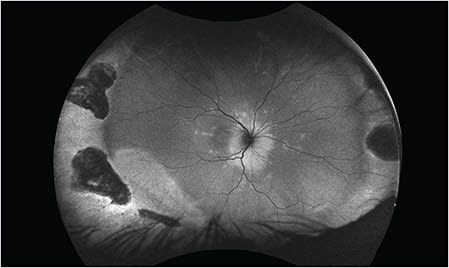

The conglomerate of white dot syndromes includes inflammatory disorders of the outer retina, retinal pigment epithelium, and choroid and is comprised of multiple evanescent white dot syndrome, acute posterior multifocal placoid pigment epitheliopathy (APMPPE), multifocal choroiditis (MFC) with or without panuveitis, punctate inner choroiditis (PIC) and acute zonal occult outer retinopathy. White dot syndromes generally present similarly in adults and children. Multiple evanescent white dot syndrome produces a granular macular appearance with tiny subretinal white or yellow lesions, while APMPPE typically has larger lesions that block early on fluorescein angiography. As with adults, neurologic symptoms can accompany the diagnosis of APMPPE and a neurological review of system is essential. MFC and PIC both have distinct subretinal lesions; MFC has vitritis and PIC does not. Acute zonal occult outer retinopathy tends to impact young women with an enlarged blind spot and ellipsoid zone changes (Figure 3). Autoflouresence can reveal zonal areas of hyperautofluorescence and hypoautoflouresnce. Patients should be monitored for the development of choroidal neovascular membranes in any of these etiologies.

Like SO, VKH is a T-cell mediated response to retinal and uveal antigens. It occurs more often in Asians, Hispanics, and Native Americans. Systemic findings include central nervous system changes, including aseptic meningitis, and cutaneous manifestations, such as vitiligo and poliosis. Pediatric cases comprise up to 15% of VKH cases and often the disease is more aggressive in children than in adults (Figure 2).16